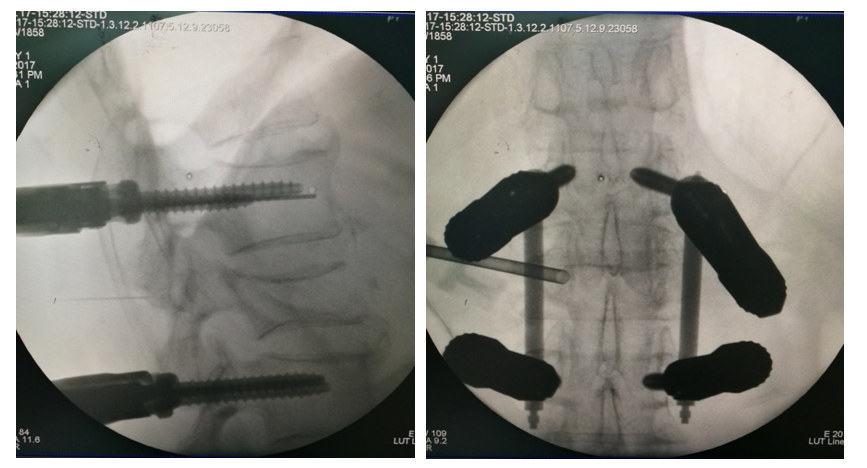

手术治疗

术后影像学

术中透视